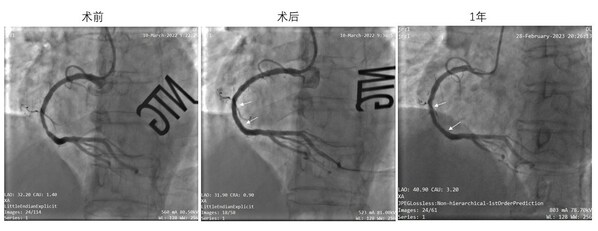

IBS®冠脈支架的可行性臨床研究(FIM,即I期臨床研究)於2018年開始受試者入組,目前已順利完成4年隨訪,結果表明其在簡單原發性冠脈病變中具有良好的中期安全有效性。血管造影(QCA)及血管內光學相幹成像(OCT)測量顯示,IBS®冠脈支架植入6個月後靶病變平均管腔面積略有增大的趨勢,說明IBS®冠脈支架逐漸降解後可能會對血管帶來正向重塑,從而有望真正體現「介入無植入」的理念和優勢。